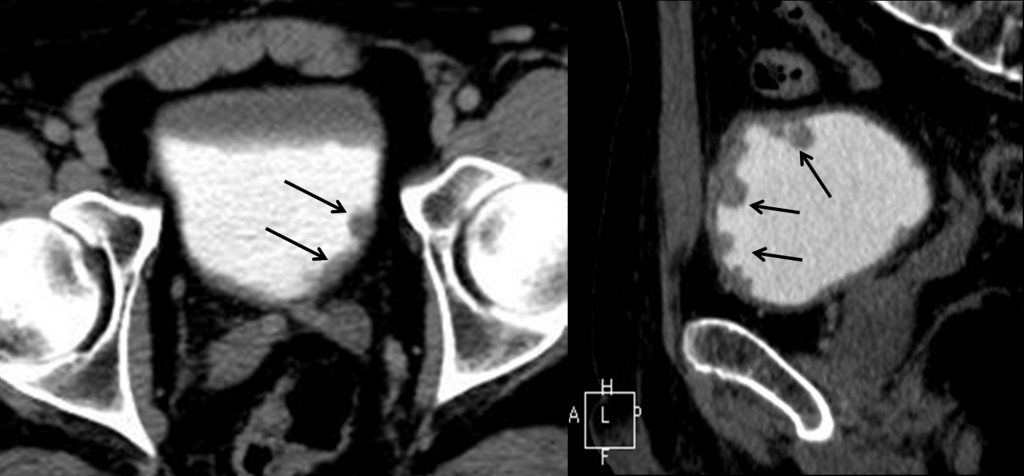

Fig. 24.4. Uroscanner chez un patient présentant une hématurie macroscopique.

Coupes axiales (A) avant injection, puis après injection au temps artériel et au temps excréteur. Coupes coronales (B) après injection, aux temps artériel et excréteur. Présence de multiples lacunes des calices (flèches) bien visibles au temps excréteur, en rapport avec des tumeurs urothéliales multiples car se rehaussant après injection.

Source : CERF, CNEBMN, 2022.